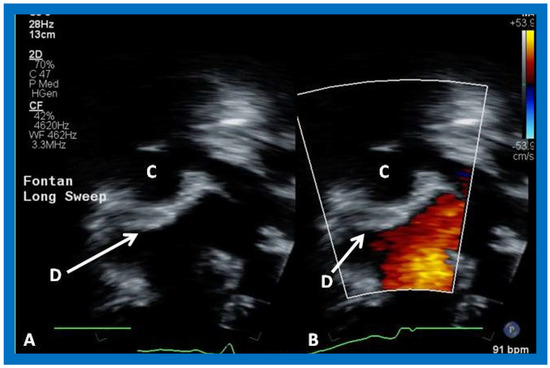

Cross-sectional views of the Fontan conduit were shown in Figure 38, Figure 39 and Figure 40. Imaging of the conduit longitudinally is also possible (Figure 46) and laminar flow in the conduit (Figure 46B) is indicative of a nonobstructive conduit. The connection between the IVC and the conduit (Figure 47 and Figure 48) can also be demonstrated by echo studies. Doppler interrogation demonstrating low flow velocities across this region (Figure 49) is indicative of nonobstructive IVC–conduit junction. Turbulent flow and high Doppler velocity across this region suggest obstruction; however, this is rarely seen.

Figure 43. Selected video frames from apical views in two dimensional (A) and color flow imaging (B) modes demonstrating the right ventricle (RV) forming a cul-de-sac connection via a ventricular septal defect (VSD) with the left ventricle (LV). ATV, atretic tricuspid tricuspid valve, C, conduit, LA, left atrium.